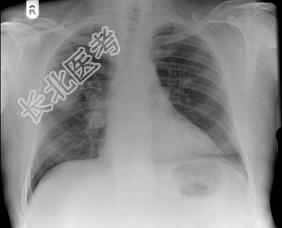

- 单项选择题58岁,男, 咳嗽、气促3个月,抽烟20余年, 请结合胸片图,选择最可能的诊断 ( )

A、肺癌

B、胸膜间皮瘤

C、肺结核

D、错构瘤

E、结节病